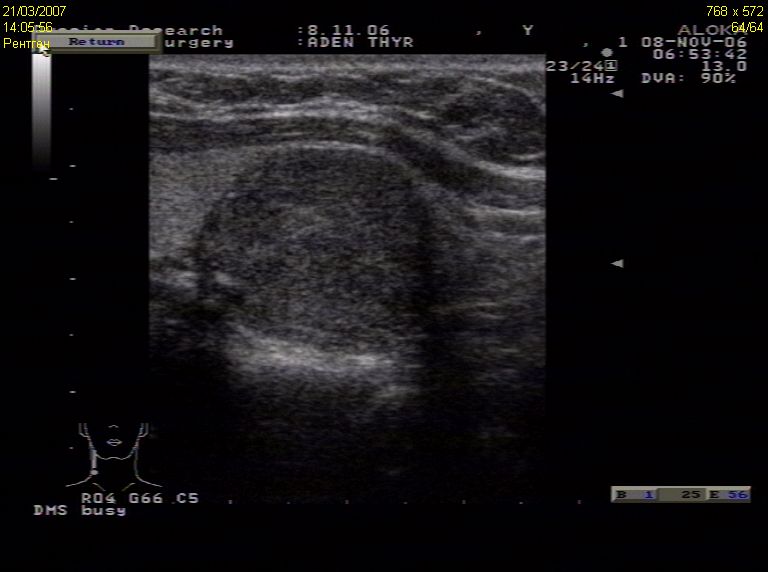

TI-RADS 4. Узлы более 1,0 см в диаметре с “малыми” признаками злокачественности для выполнения ПУНКЦИИ (рис. 3):

- солидные узлы, равномерно или неравномерно умеренно пониженной эхогенности;

- солидные узлы изо- или гиперэхогенные, имеющие “малые” признаки злокачественности:

– гипоэхогенные включения;

– округлая/шаровидная форма;

– неравномерно утолщенное хало;

– макрокальцинаты.

Рис. 3. TI-RADS 4: а – узел шаровидной формы, с ровными и четкими контурами, умеренно пониженной эхогенности, с участками более низкого эхо, с макрокальцинатом. Узел окружен тонким хало (фолликулярная неоплазия); б, в, г (поперечное и продольное сканирование левой доли ЩЖ) – изоэхогенные узлы с гипоэхогенными включениями, с четкими контурами, с тонким хало (фолликулярная аденома); д – изоэхогенный узел с гипоэхогенными включениями, с неравномерно утолщенным хало (фолликулярный рак).